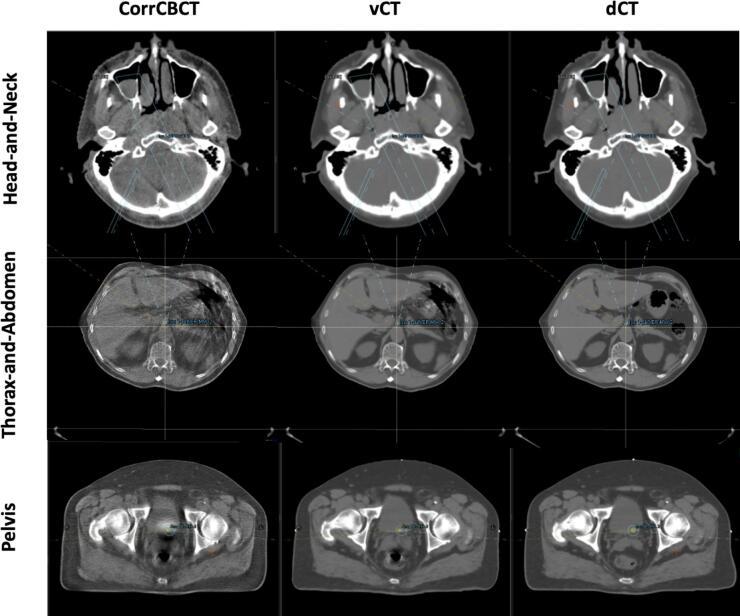

The evaluation was conducted for head-and-neck, thorax-and-abdomen, and pelvis sites treated with proton therapy. Thirty patients with two cone-beam computed tomography (CBCT) scans each were selected. The sCT images were generated from CBCT scans using two algorithms, Corrected CBCT (corrCBCT) and Virtual CT (vCT). Dose recalculations were performed based on these images for comparison with "ground truth" deformed CTs.

The choice of algorithm influenced dose recalculation accuracy, particularly in high dose regions. For head-and-neck cases, the corrCBCT method showed closer agreement with the "ground truth", while for thorax-and-abdomen and pelvis cases, the vCT algorithm yielded better results (mean percentage dose discrepancy of 0.6 %, 1.3 % and 0.5 % for the three sites, respectively, in the high dose region). Head-and-neck and pelvis cases exhibited excellent agreement in high dose regions (2 %/2 mm gamma passing rate >98 %), while thorax-and-abdomen cases exhibited the largest differences, suggesting caution in sCT algorithm usage for this site. Significant systematic differences were observed in the clinical target volume and organ-at-risk doses in head-and-neck and pelvis cases, highlighting the importance of using the correct algorithm.